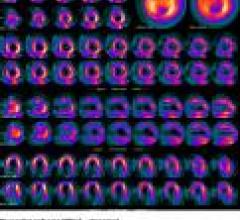

November 12, 2009 - Centers for Medicare & Medicaid Services' (CMS) will expand coverage of FDG-PET for the initial staging of cervical cancer without previously imposed restrictions.

November 12, 2009 - Positron Corp. predicts an industry wide demand for cardiac PET imaging, as a result of the Centers for Medicare & Medicaid Services (CMS) 2010 Medicare Physician Fee Schedule increasing Cardiac PET reimbursement by 20 percent, while reducing coverage for SPECT by 36 percent.